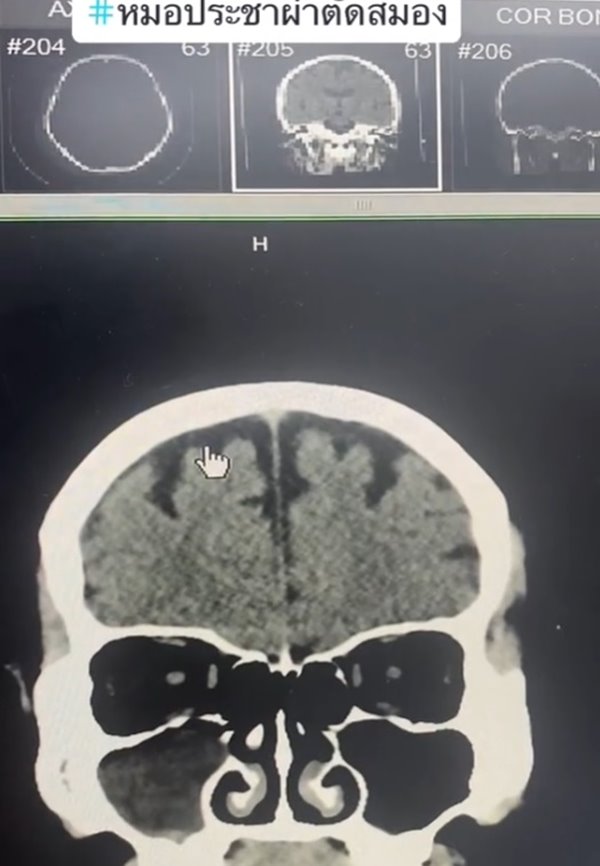

เปิดภาพเทียบให้ดูชัด ๆ สมองคนทั่วไปกับคนติดเหล้า เห็นภาพซีทีสแกนชัดเจน พบคนกินเหล้าจะมีอาการสมองฝ่อ ล้มนิดเดียวเลือดออกในสมอง ต่างกับคนทั่วไปชัดเจน ใครกินเหล้าต้องคิดให้ดี

เราอาจจะรู้กันว่า การติดเหล้านั้นมีผลทำให้เป็นโรคตับแข็ง และเป็นปัจจัยที่ทำให้เกิดโรคร้ายต่าง ๆ ตามมาได้มาก แต่ในความเป็นจริงแล้ว การดื่มเหล้าและมีอาการติดเหล้า ก็ส่งผลต่อสมองได้เช่นกัน และล่าสุดก็มีภาพซีทีสแกนมายืนยันในเรื่องนี้แล้ว

วันที่ 30 กรกฎาคม 2566 TikTok @doctor.pracha_neuro_surg ของ นพ.ประชา กัญญาประสิทธิ์ ประสาทศัลยแพทย์ มีการเล่าเรื่องราวประสบการณ์การผ่าตัดสมอง พร้อมข้อเตือนใจประชาชน โดยเปรียบเทียบกันระหว่าง สมองคนทั่วไปกับสมองคนที่ติดเหล้า มันต่างกันอย่างไรบ้าง คลิปนี้มีคนดูมากกว่า 1 ล้านครั้ง

หมอประชายังเล่าเพิ่มเติมว่า คนที่ดื่มเหล้าบ่อย ๆ เวลาล้มหัวกระแทก จะทำให้เลือดออกได้ง่าย เพราะเนื้อที่สมองน้อย ผลกระทบอื่น ๆ ก็ยังมีโอกาสเป็นเบาหวาน ไขมัน โอกาสอัมพาตจากสโตรก ดังนั้น มีโอกาสเสียชีวิตหรือพิการมากกว่าคนทั่วไป